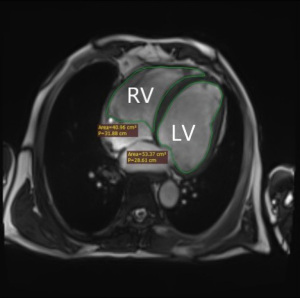

Left atrial volume (LAV), calculated as LAV = (0.848 × area4ch × area2ch)/[length4ch + length2ch)/2] (Figure 1A,1B), reflects LV diastolic dysfunction (63,64). LAV effectively differentiates PAH from PH due to left heart disease (PH-LHD). The area under the curve (AUC) for distinguishing idiopathic PAH (IPAH) from PH due to heart failure with preserved ejection fraction (PH-HFpEF) with LAV <43 mL/m2 was 0.99 (sensitivity 97%, specificity 100%) (26). In addition, LAV also performed well in classifying precapillary PH (pre-PH) and postcapillary PH (post-PH) (27), with an AUC of 0.96. Apart from the diagnostic and classification value, LAV has shown to be of great clinical importance in predicting the prognosis of PH. A study showed that LAV index (LAVi) was an independent predictor of mortality in CTEPH patients undergoing pulmonary endarterectomy (PEA), highlighting the importance of evaluating left heart structures in CTEPH patients undergoing PEA (28).

LV structure (Figure 1C,1D) has also shown significant value in PH management. A study of PH in 30 patients with aortic stenosis (AS) found that the LV end-diastolic volume index (LVEDVi) >107.7 mL/m2 was a significant predictor of PH in severe AS (AUC 0.957, sensitivity 100%, specificity 87%) (29). In addition, LVEDVi has shown a prognostic correlation with PAH. van Wolferen et al. (9) showed that LVEDVi ≤40 mL/m2 was significantly associated with decreased 1-year survival in IPAH, suggesting its utility as a follow-up indicator. A prognostic analysis of 576 PAH patients by Swift et al. (30) also confirmed that reduced LVEDVi is associated with increased all-cause mortality risk in PAH.